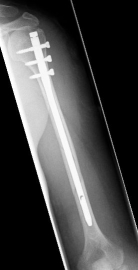

Oberarmschaftbruch3Oberarmschaftbruch4Oberarmschaftbruch5

Picture: An upper arm shaft fracture can alternatively be stabilized by a plate that bridges the fracture. The picture shows a shaft fracture with a bending wedge. After surgical treatment, the upper arm shaft is back in the correct axis.